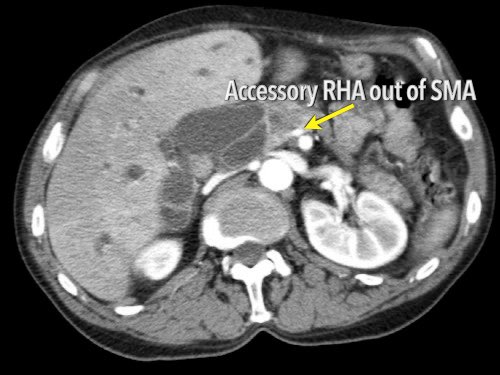

Các biến thể giải phẫu động mạch

Các biến thể giải phẫu

Giải phẫu động mạch gan được coi là bình thường chỉ gặp ở 55% dân số (hình minh họa).

Các biến thể giải phẫu động mạch gan được ghi nhận ở khoảng 40-45% dân số.

Các động mạch bất thường có thể đi qua vùng lân cận đầu tụy, làm tăng nguy cơ xâm lấn của khối u hoặc tổn thương do phẫu thuật.

Các động mạch gan có nguyên ủy bất thường có thể là dạng phụ thêm (accessory) hoặc dạng thay thế (replaced).

Động mạch gan phải phụ thêm là một động mạch gan phải bổ sung, trong khi động mạch gan phải thay thế có nguyên ủy bất thường và thay thế hoàn toàn cho động mạch gan phải chính thức (hình minh họa).

Ở những bệnh nhân dự kiến phẫu thuật tụy, điều quan trọng là cần đặc biệt chú ý tìm kiếm nguyên ủy bất thường của động mạch gan phải hoặc động mạch gan chung.

Các động mạch này xuất phát từ phía phải của động mạch mạc treo tràng trên (SMA) và đi qua vùng lân cận đầu tụy, làm tăng nguy cơ xâm lấn của khối u hoặc tổn thương do phẫu thuật.

Tần suất được ghi nhận của các bất thường đặc hiệu này lần lượt là 11-21% và 0,5-5%.

Hình CT axial cho thấy một động mạch gan phải phụ thêm (mũi tên vàng) đi qua vùng lân cận một khối giảm tỷ trọng ở đầu tụy (đầu mũi tên).